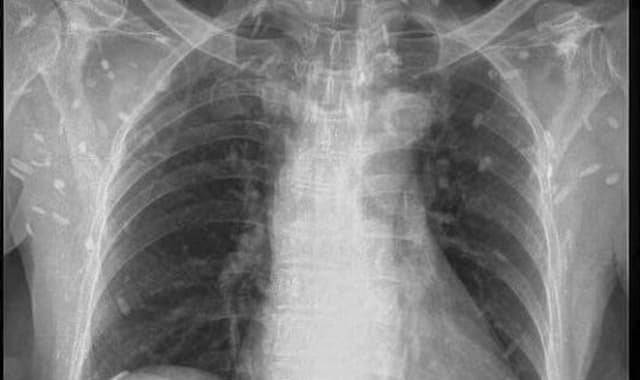

Chụp X-quang tim phổi thẳng phát hiện sớm những bất thường

Chụp X-quang tim phổi thẳng là một trong những phương pháp giúp phát hiện sớm những bất thường ở tim, phổi và các cơ quan lân cận. Đây là một phương pháp được ứng dụng rộng rãi trong việc chẩn đoán hình ảnh, tìm ra những bất ổn để kịp thời xử lý. Chụp X-quang (ray) […]